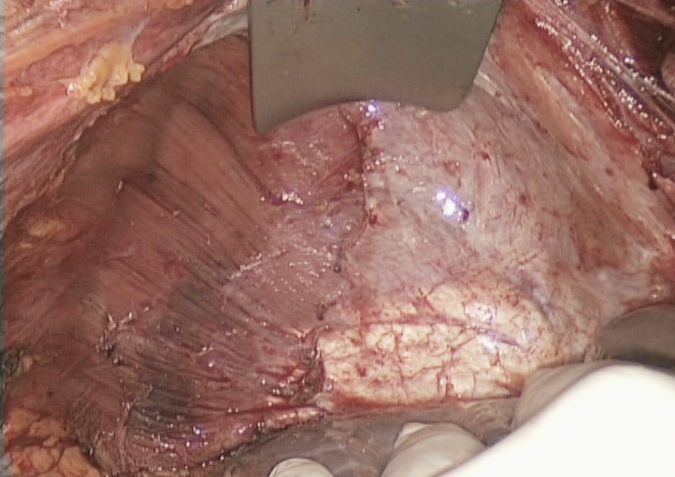

4月15日-21日是第29届全国肿瘤防治宣传周。卵巢癌的诊治是妇科肿瘤防治的重点,卵巢癌的手术质量显著影响预后。本文介绍晚期卵巢癌膈肌手术的分型-Tozzi分型,由牛津大学教授、帕多瓦大学附属医院妇产科主任Tozzi教授总结提出,南方科技大学医院妇科潘宏信教授翻译介绍。供同行参考交流。 由于缺乏特异性症状,约3/4的卵巢癌患者发现时已处于晚期(国际妇产科联盟分期ⅲc-ⅳ期)。肿瘤细胞减灭术仍然是这些患者治疗的基石,无论是作为主要治疗方式还是新辅助化疗后的治疗方式。无论手术时机如何,术后肿瘤残留病灶均显著影响预后[1-9]。完全切除(complete resection CR)与最佳的总生存率和无病生存率[5]相关。超过70%的患者出现膈肌和肝脏的腹膜的转移。1/4的患者病变累及膈肌全层[8,9]。膈肌手术包括膈肌腹膜切除,膈肌腹膜、膈肌肌层和胸膜,并进入胸腔。由于希望实现R0手术的妇科肿瘤医生常常面临膈肌的手术,因此在过去10年中,膈肌手术已被纳入肿瘤细胞减灭术。从第一篇关于卵巢癌患者膈肌病灶手术切除的报道以来已经过去了近30年,对于膈肌病变的模式和所需的手术范围仍未有系统的分类。这使得手术规划、评估所需要的围手术期支持、发病率数据的统计和比较变得困难。此外,在没有分类的情况下,无法评估实施膈肌手术所需的专科培训水平。欧洲妇科内镜学会SIG肿瘤学主席、帕多瓦大学附属医院妇产科主任、牛津大学教授Roberto Tozzi在Journal of gynecologic oncology上发表了一项研究,针对膈肌手术提出了分型(Tozzi分型)。本文对该分型做介绍。 入组标准 可疑或者病理证实是IIIC–IV期卵巢癌 美国东部肿瘤协作组体力状况(Eastern Cooperative Oncology Groupperformance status,ECOGPS)评分<2分 接受3-6个周期化疗后病情稳定者 排除标准 术前CT扫描显示肺转移,3个或3个以上肝段受累和/或化疗后疾病进展 腹腔镜探查示弥漫性小肠浆膜、肝门包膜转移病灶